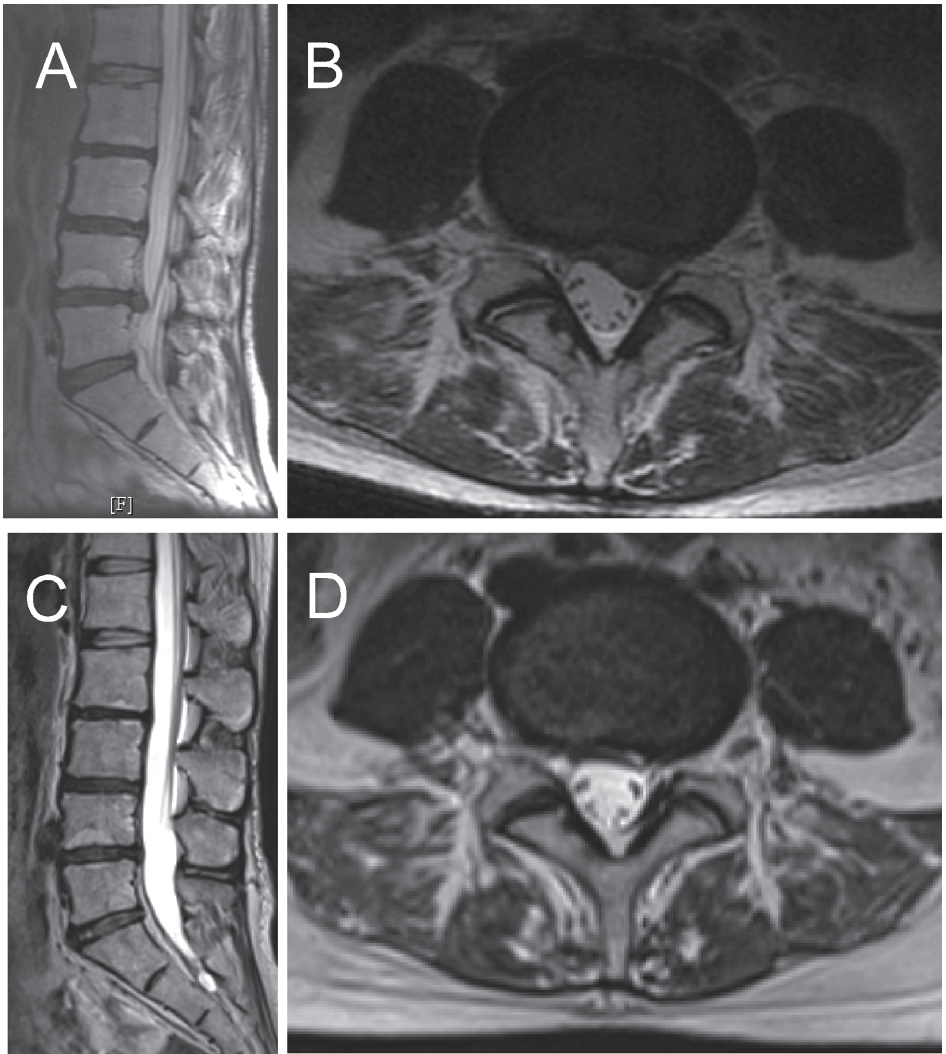

Грыжа поясничного диска с контралатеральными симптомами: как такое вообще возможно?